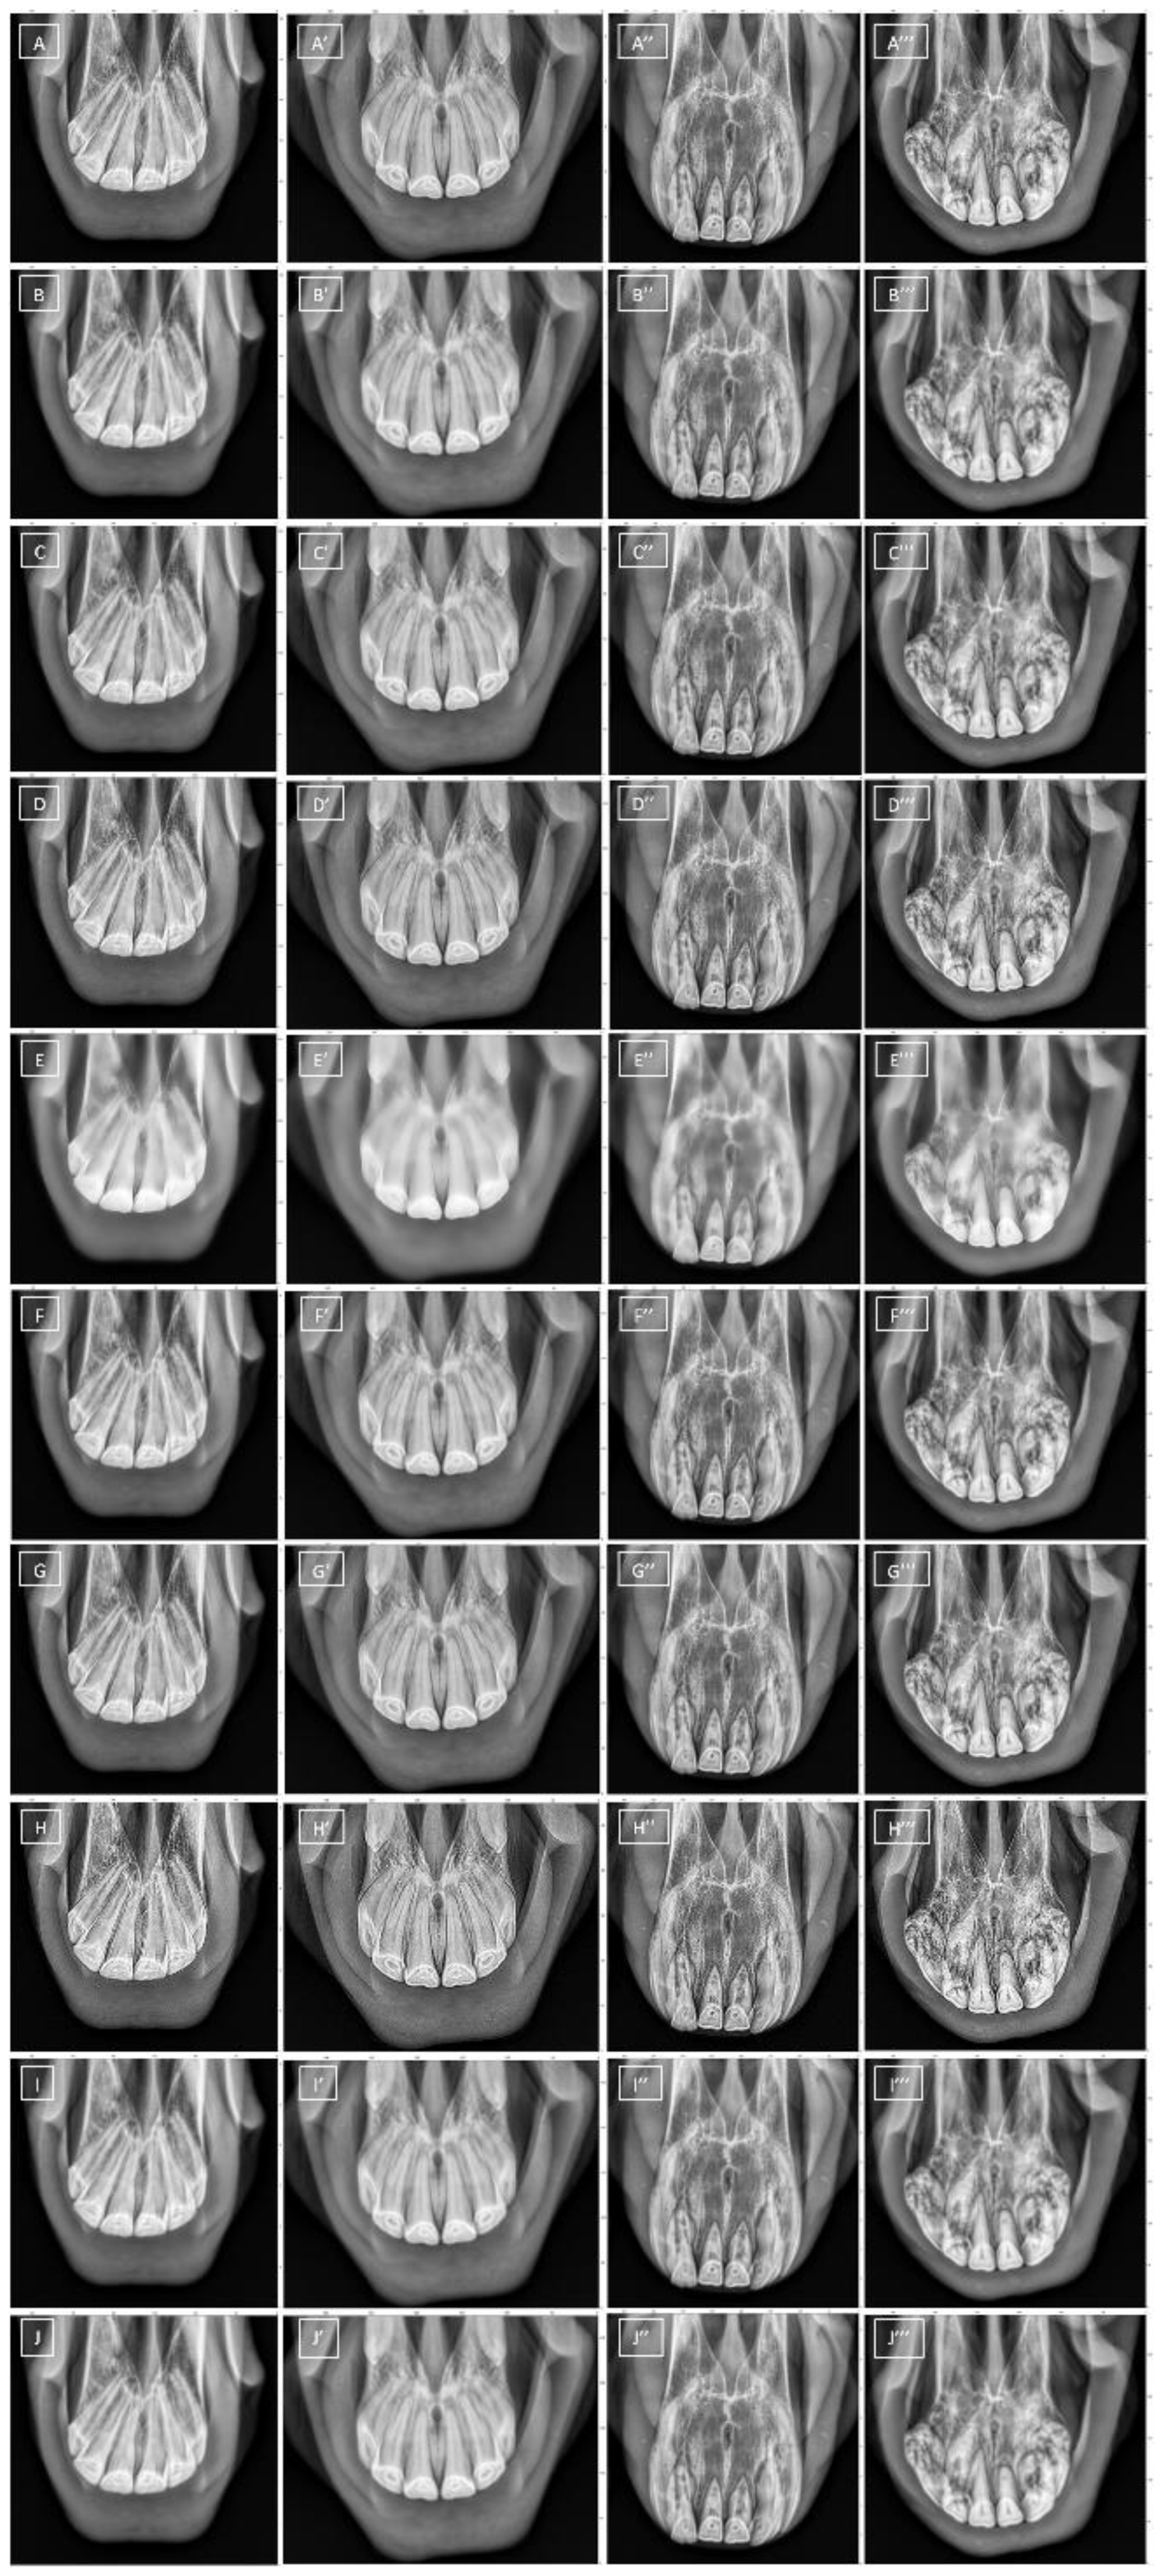

2.3.2. Filtering